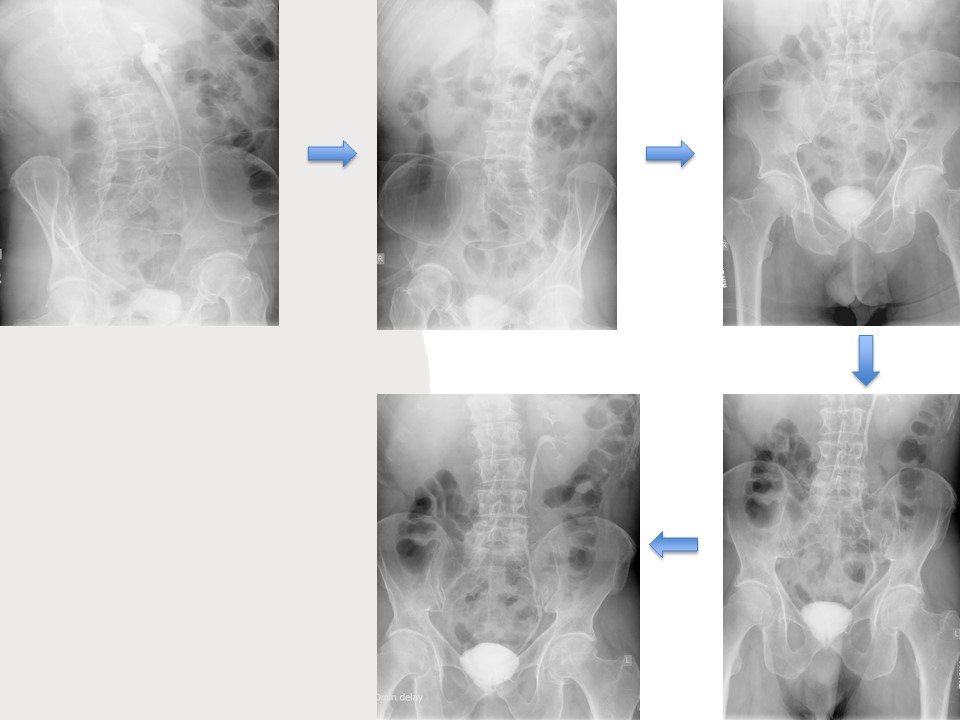

The right kidney and ureter were not visualized on intravenous urography until 60 min. The left kidney and ureter revealed normal.

On the 20 min post-void image there is opacification of the right kidney (delayed nephrogram), still without any contrast in the collecting system, compatible with high-grade obstruction of the right collecting system.